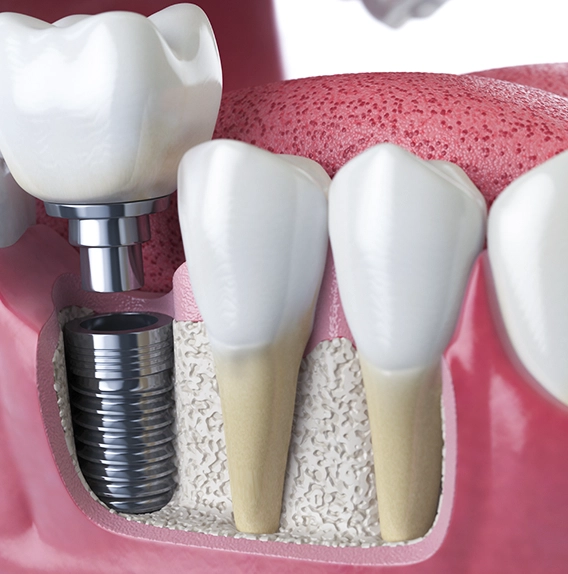

O que são implantes dentários

Os implantes dentários são atualmente a forma mais moderna, segura e previsível de devolver a função mastigatória, a estética e a qualidade de vida a pacientes que perderam um ou mais dentes, seja por extrações já realizadas ou por necessidades futuras.

O tratamento consiste na instalação cirúrgica de pinos de titânio no osso maxilar ou mandibular. Esses pinos atuam como raízes artificiais, servindo de base para coroas em porcelana ou próteses fixas.

O titânio é um material biocompatível, amplamente utilizado na área da saúde, que não causa rejeição. Essa característica garante alta taxa de integração ao osso, além de segurança no procedimento e previsibilidade nos resultados.